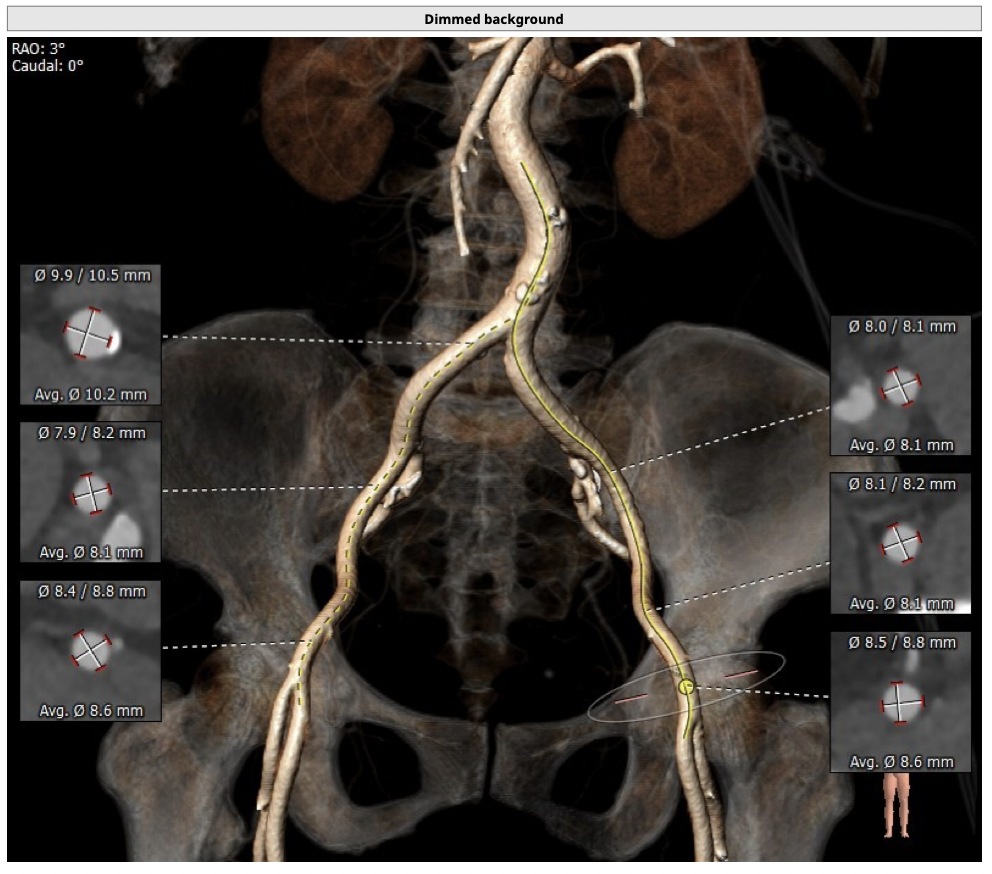

主动脉CT

*心脏角度为57°,横位心,输送器过瓣难度增加,瓣膜植入同轴性差,瓣膜释放更易移位,增加了操作的难度;

经分析研判,拟从右侧股动脉穿刺入路,使用20mm球囊预扩,采取downsize手术策略,选用L23号的VenusA-Valve瓣膜,因患者为横位心,瓣膜释放同轴性差,容易发生移位,故采用VenusA-Plus可回收输送系统确保瓣膜的稳定释放,瓣膜释放后结合造影和超声情况,决定是否后扩。